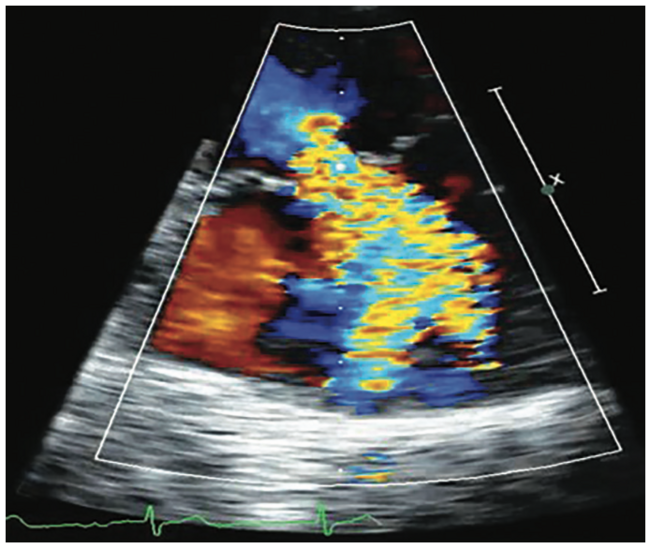

This case of transcatheter edge-to-edge repair (TEER) with a MitraClip device (Abbott) demonstrates how 4D volume intracardiac echocardiography (ICE) catheter imaging (ACUSON AcuNav Volume ICE catheter on the ACUSON SC2000 PRIME ultrasound system, Siemens Healthineers) enables the treatment of patients with severe mitral regurgitation who otherwise would have no options for care.

A 38-year-old female with significant osteogenesis imperfecta, severe scoliosis, and severe myxomatous mitral valve was referred for TEER. An adult transesophageal (TEE) transducer could not be used due to the severe scoliosis, and pediatric TEE imaging was suboptimal for use in the procedure. Preprocedural transthoracic echocardiogram demonstrated severe mitral regurgitation. The 4D ICE catheter assisted with transseptal puncture at the optimal superior and posterior positions, with the circle tool verifying the 4.5 cm distance from the mitral annular plane. Biplane imaging using reference planes with and without color helped guide the device to the optimal position. Physicians were able to treat the patient with relative or absolute contraindication to TEE.